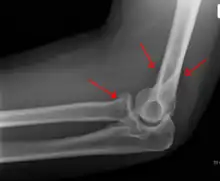

- Proximal radius fracture. A fracture within the capsule of the elbow joint results in the fat pad sign or "sail sign" which is a displacement of the fat pad at the elbow.